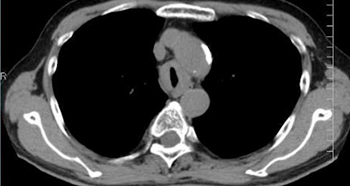

□CT

所見としては気管を取り囲むように濃度上昇域があり、さらなる精査が必要です。